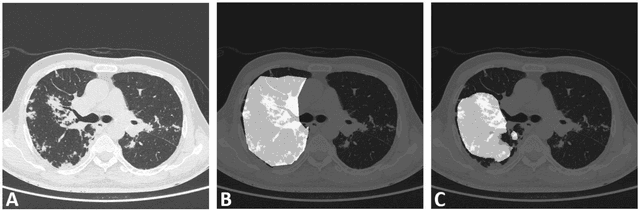

Abstract:Image segmentation plays a pivotal role in several medical-imaging applications by assisting the segmentation of the regions of interest. Deep learning-based approaches have been widely adopted for semantic segmentation of medical data. In recent years, in addition to 2D deep learning architectures, 3D architectures have been employed as the predictive algorithms for 3D medical image data. In this paper, we propose a 3D stack-based deep learning technique for segmenting manifestations of consolidation and ground-glass opacities in 3D Computed Tomography (CT) scans. We also present a comparison based on the segmentation results, the contextual information retained, and the inference time between this 3D technique and a traditional 2D deep learning technique. We also define the area-plot, which represents the peculiar pattern observed in the slice-wise areas of the pathology regions predicted by these deep learning models. In our exhaustive evaluation, 3D technique performs better than the 2D technique for the segmentation of CT scans. We get dice scores of 79% and 73% for the 3D and the 2D techniques respectively. The 3D technique results in a 5X reduction in the inference time compared to the 2D technique. Results also show that the area-plots predicted by the 3D model are more similar to the ground truth than those predicted by the 2D model. We also show how increasing the amount of contextual information retained during the training can improve the 3D model's performance.